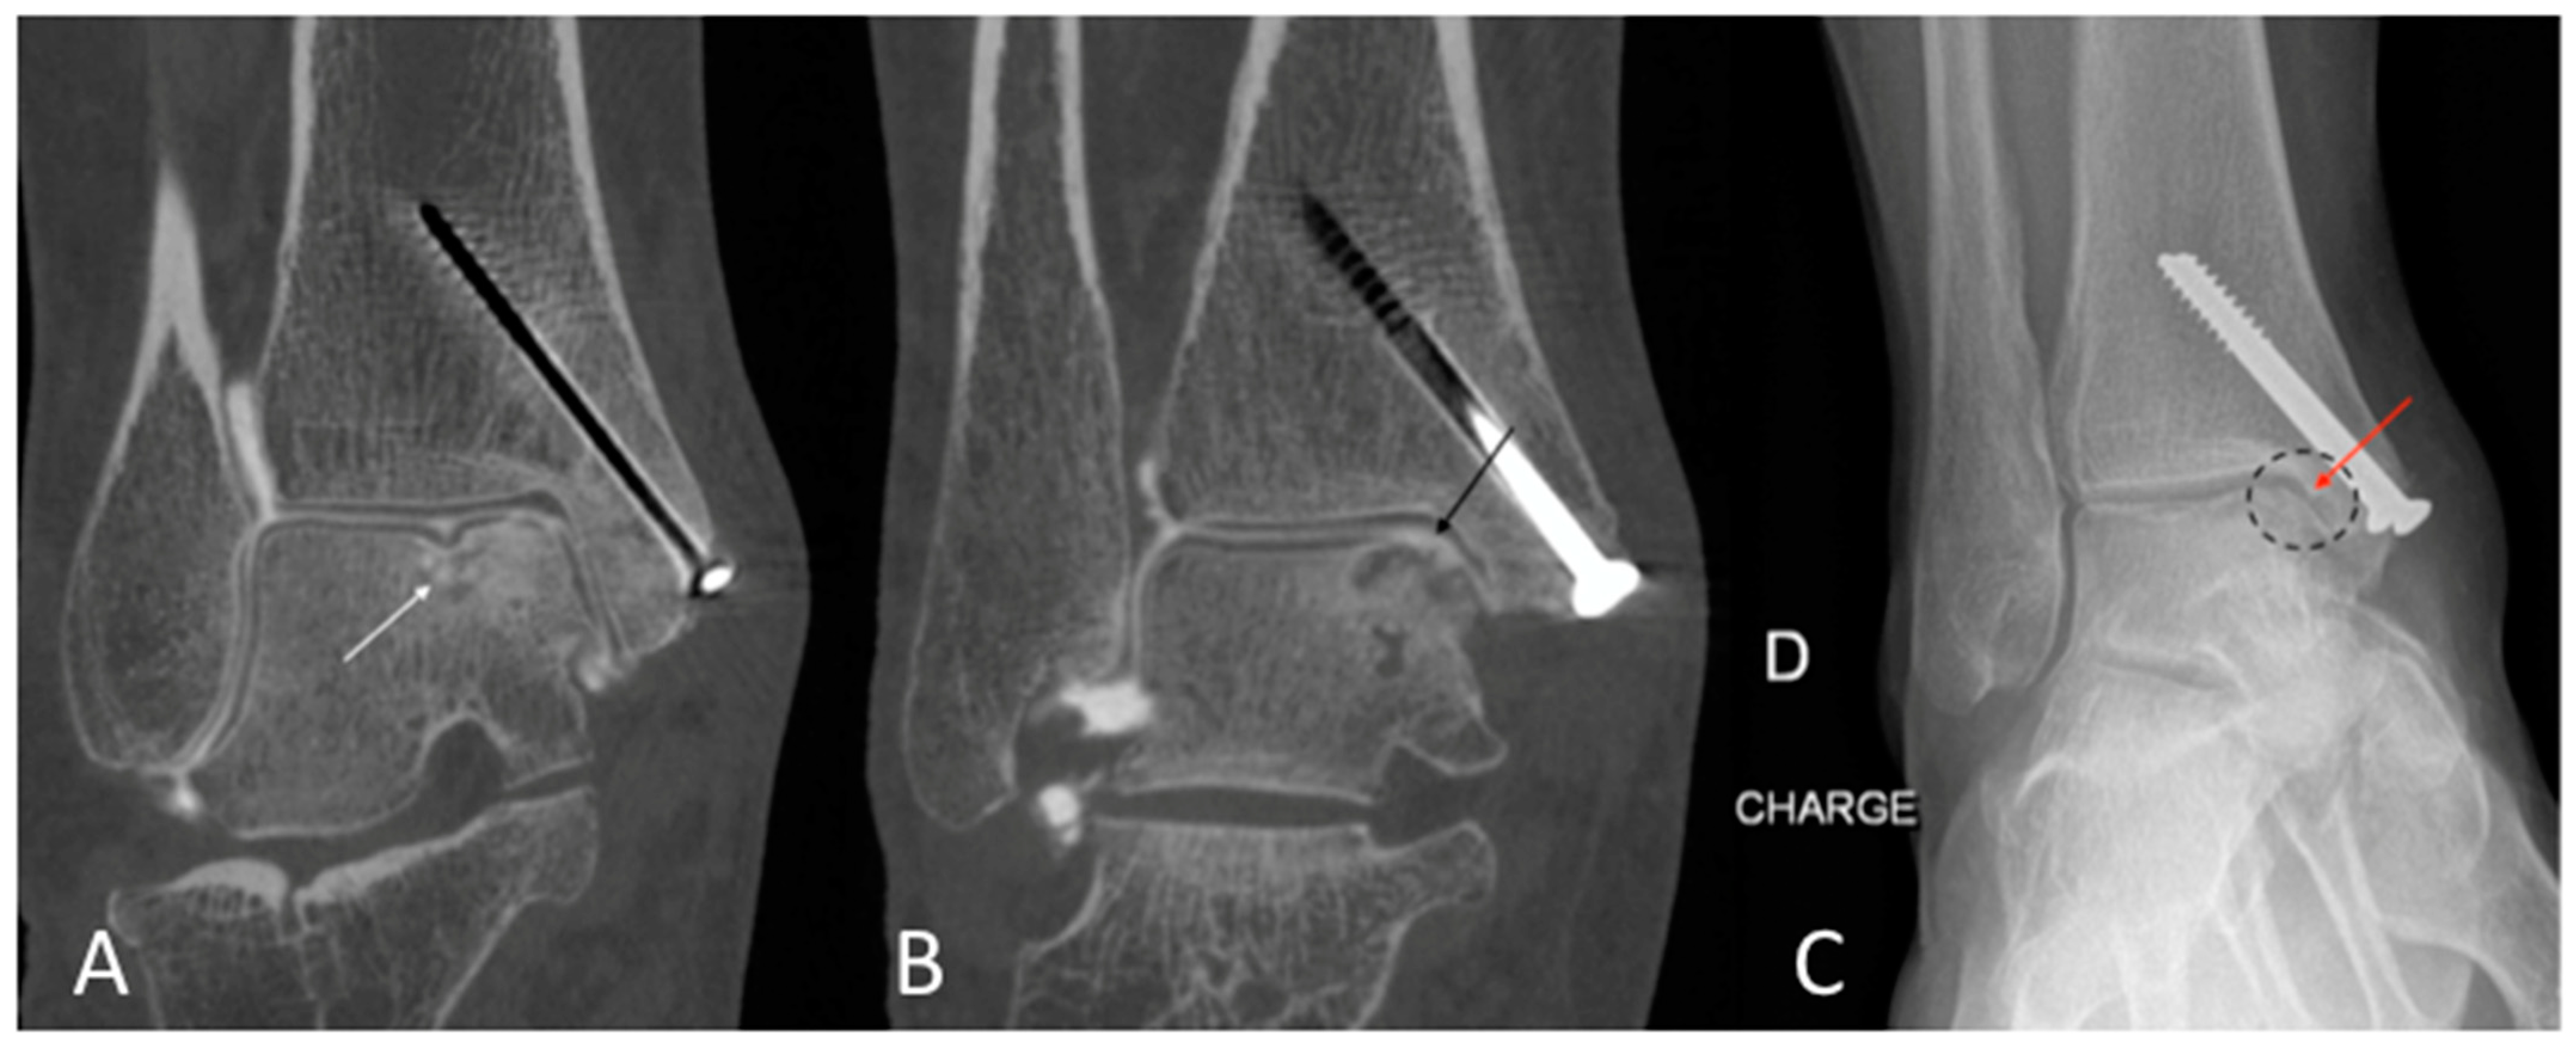

Figure 6. CBCT-A of left wrist in coronal (A) and sagittal (B) planes, which showed sub chondral erosion ((A) white arrow) and definite anterior osteophyte of the radial lip ((B) red arrow), grade 3 of the KLC scoring system. The AP DR showed a possible joint space narrowing between the scaphoid and radial styloid ((C) dark dotted circle), grade 2 of KLC scoring system. The KLC scoring based on DR is underestimated compared to CBCT-A. As osteoarthritis was confirmed between the radius and scaphoid bone surfaces, scaphoidectomy was performed for this patient instead of styloidectomy considered initially based on DR analysis. CBCT-A: cone-beam computed tomography arthrography; DR: digital radiography; KLC: Kellgren and Lawrence classification.

The qualitative image analysis was excellent in all CBCT-A cases corresponding to the best scale for image quality, with an excellent inter-observer concordance (kappa = 1), as shown in Figure 4, Figure 6, and Figure 7. Twenty-four patients had an OA diagnosis (KLC ≥ 2) with the CBCT-A, and twenty-one were subclassed with DR. No statistically significant difference was observed in terms of sclerosis (p = 0.29) and erosion (p = 0.184) between both modalities. Examples of OA underestimation, with DR compared with CBCT-A, are shown in Figure 6.

Concerning the quantitative image analysis, OA under-classification was noticed with DR regarding the MJW (p = 0.02), detection of osteophytes (<0.0001), and KLC (p < 0.0001), as shown in Table 3.